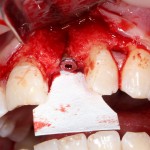

Например, в следующей ситуации:

Оставить так, как есть — это значит, сильно рисковать имплантом и объемом альвеолярного гребня — фактически, большая часть импланта пятого зуба «висит в воздухе». Поэтому получившуюся костную полость мы заполняем аутокостной стружкой в смеси с Bioss и закрываем коллагеновой мембраной BioGide: